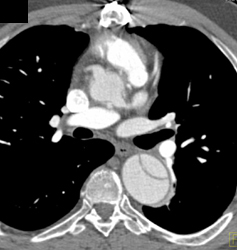

Diagnosis

Type B Dissection